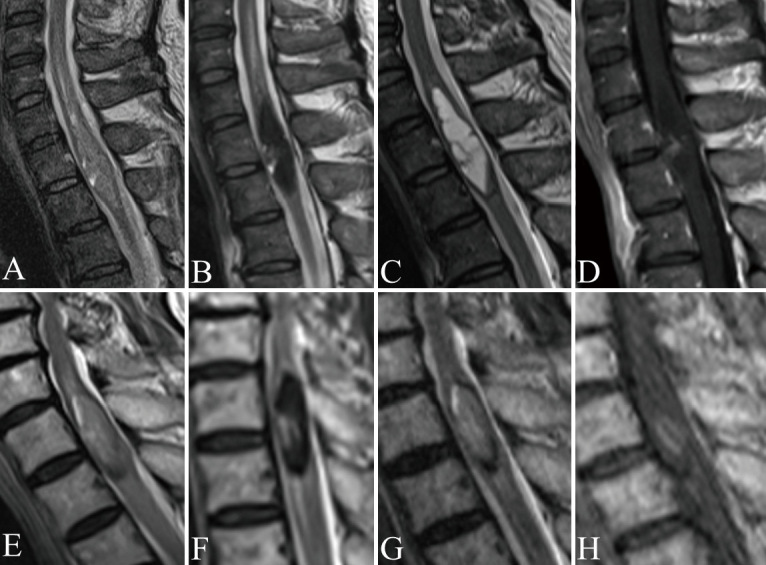

Spinal ependymomas are common intramedullary tumors that can show dynamic changes in magnetic resonance imaging findings over time. This study aimed to analyze these imaging changes and their implications for perioperative management. The retrospective study included patients diagnosed with World Health Organization grade 2 spinal ependymoma who underwent surgical resection and had at least 2 preoperative magnetic resonance imaging scans. Patients were divided into 2 groups based on the presence or absence of radiographic changes on magnetic resonance imaging. Magnetic resonance imaging analyses included non-contrast T1- and T2-weighted images, as well as gadolinium-enhanced T1-weighted images when available. Key features evaluated included intraparenchymal edema, hemosiderin deposition, syringomyelia, and cyst components. Changes in tumor size and contrast enhancement patterns were documented. Radiographic changes were identified in 4 out of 15 cases (26.7%). All cases with imaging changes exhibited hemosiderin deposition or hemorrhage, significantly higher than in cases without changes (100% vs. 18.2%, p < 0.05). No significant differences were observed in the presence of cystic components, syringomyelia, or edema between the groups. In the group with radiographic changes, the timeframe for these changes in the images ranged from 3 days to several years. Spinal ependymomas can demonstrate dynamic magnetic resonance imaging changes during the preoperative period, including both growth and reduction in tumor size. The presence of hemosiderin deposition or hemorrhage might be associated with these imaging changes. Proper timing of magnetic resonance imaging is crucial for informing surgical planning and optimizing treatment strategies for patients with spinal ependymomas.

Abstract Image